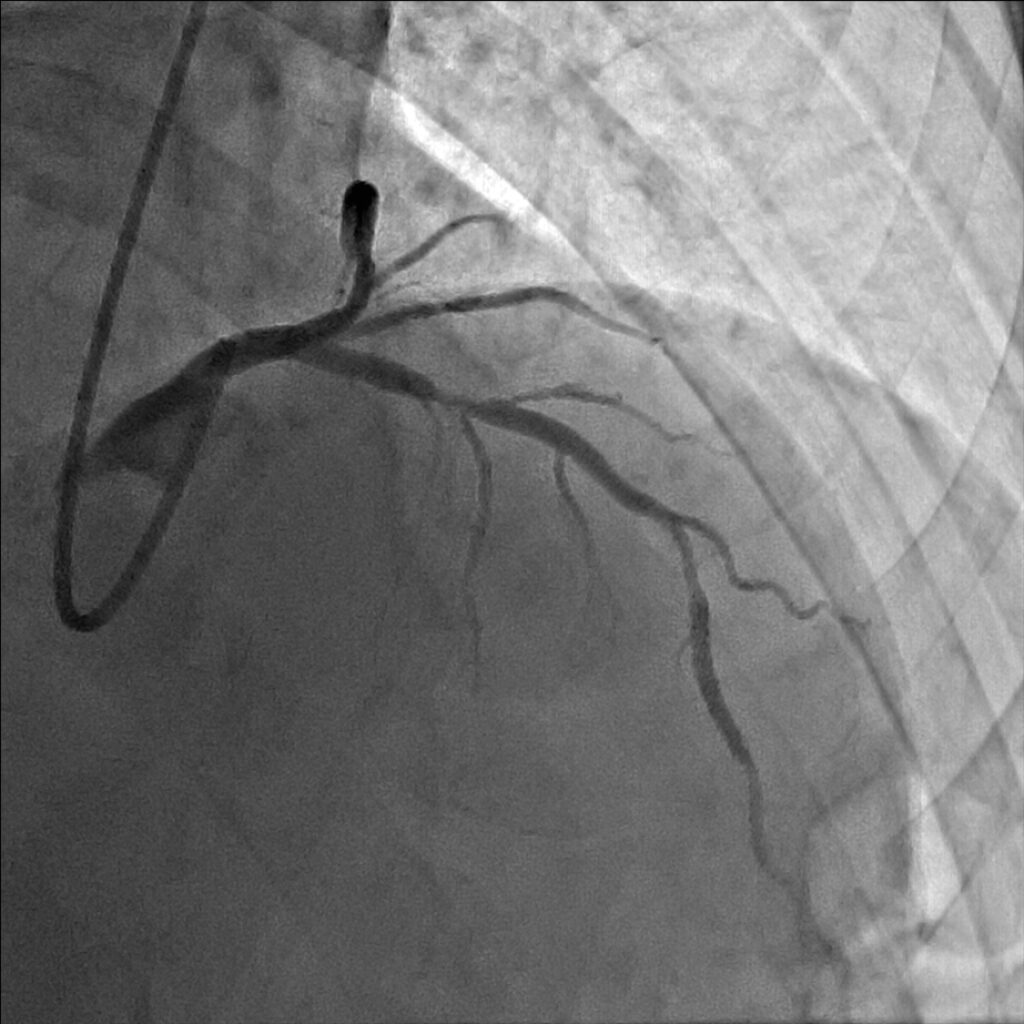

妻の勧めで近所の医院を受診しました。安静時心電図検査では何の異常もなかったのですが、念のためにと私の外来を紹介されました。ベルトコンベアーの上を歩く運動負荷心電図検査でいつもと同じような症状を覚え、心電図に異常が出現しました。私は労作性狭心症と診断しました。手首からカテーテルを挿入した冠動脈造影検査で、一番大きな冠動脈枝の近位部に高度な狭窄が見つかりました。後日、風船とステントを用い、狭窄を開大しました。症状は完全に消失し、今は農作業に精を出しています。

狭心症は“心臓を狭める”という症状から由来した病名です。疑わしい症状がある方は、上記の症状に合致するかをチェックしてみて下さい。専門医は症状を詳細に聴取するだけで80%以上の診断が可能です。労作性狭心症を裏付ける検査としては、運動負荷試験が最も一般的です。心電図や血圧計を装着し、ベルトコンベアーの上を歩きます。速度や勾配を段階的に上げることで心筋に徐々に負荷をかけていきます。いつもの症状が出たとき、心電図異常が出現したとき、負荷が標的水準までかかったときに中止します。この検査は診断率が高くかつ安全です。最終的には造影剤を使ったCT検査やカテーテル検査で狭心症の診断のみならず、冠動脈狭窄の程度や部位、病変部数等を精査します。